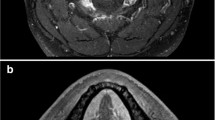

Four hundred ninety-five patients in the collection of data from The Cancer Imaging Archive (TCIA) [42] were included in the study. The study only examined 238 individuals’ contrast-enhanced CT scans, 204 of whom were HPV positive and had been given an OPC diagnosis. The gross primary tumor volume (GTVp) (see Fig. 1), which is divided by experts, is taken into account in radiomic research [35].

After performing image preprocessing, the feature extraction process was carried out using 3D Slicer software (version 5.0.3) [45]. A standard bin width of 10 was set in order to implement gray-level discretization and reduce variability [46]. These included characteristics of the original images, wavelet-transformed images, and Laplacian of Gaussian (Log)-filtered images (see Fig. 2). After the images have been converted into features, the newly generated data were utilized to train and evaluate machine learning (ML) models. These characteristics can be used to perform quantitative image comparisons [47]. van Griethuysen et al. [48] have detailed explanations of the radiomics technique.